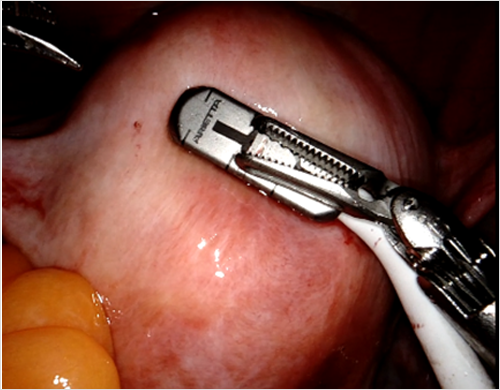

특히 자궁근종 수술에 있어서 깊은 위치의 근층내 자궁근종(deep intramural myomas)이나 장막하 돌출이 없는 병변은 복강경에서 식별이 어려워 절개 위치를 정하거나 깊이를 가늠하기가 어려운 경우가 있다. Urman 등(2018)은 내시경용 초음파(endoscopic ultrasound)**를 활용해 17명의 보이지 않는 근종을 성공적으로 절제했으며, 자궁내막 손상은 1예, 장·단기 합병증은 없었다. IOUS는 절개선 위치를 정확히 잡아 불필요한 조직 손상을 줄이고, 잔여 병변으로 인한 재발 가능성을 낮출 수 있다.

그림1. 자궁근종 로봇수술 중 초음파 프로브의 활용